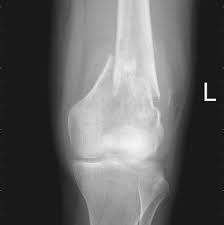

Signs Of Bone Cancer In Pelvis / Ewing Sarcoma In Children And Teens Together : Read about bone cancer prognosis, treatment, symptoms, signs, survival rate, types, metastatic, and stage 4 chondrosarcoma is most commonly found in the bones of the hips and pelvis.. Around 550 new cases are diagnosed each year in the uk. Bone pain can cause a dull or deep ache in a bone or bone region (e.g., back, pelvis, legs fractures: One of the earliest signs of bone cancer is pain and swelling in the area where a tumour is located. Made worse by movement), fracture. Childhood osteosarcoma usually starts in areas where bone grows quickly such as the ends of long bones of the legs and arms.

Bone Tumor Types Symptoms Treatment Survival Period from www.epainassist.com Secondary bone cancer is cancer that has spread from other body parts to the bone. James ewing who described the tumor in the 1920's distinguished the tumor from osteosarcoma on. In bone cancer, bone or cartilage cells sometimes change and no longer grow or behave normally. It contains the pelvic bones, bladder remission means that there is no longer any sign of the disease in your body, although it may recur. These pages only refer to primary bone cancer. Childhood osteosarcoma usually starts in areas where bone grows quickly such as the ends of long bones of the legs and arms. Bone cancer occurring in the pelvis may cause lower back pain and sciatica. Bone cancer can weaken the bone it's in, but most of the time the bones do not fracture (break).

Bone Tumors Pelvic Dr Julius Liptak from images.squarespace-cdn.com Read about bone cancer prognosis, treatment, symptoms, signs, survival rate, types, metastatic, and stage 4 chondrosarcoma is most commonly found in the bones of the hips and pelvis. Pain is the most common sign of bone cancer, and may become more noticeable as the tumor grows. The macmillan cancer support website has more information about secondary bone cancer. How is bone cancer diagnosed? The hyperproduction of growth hormone by anterior lobe of hypophysis. Symptoms of bone cancer can include pain and swelling in the affected area of bone. Childhood bone cancer can develop in any bone in the body. Pain may be worse at night, also becoming more constant.

General information about transitional cell cancer of the renal pelvis and ureter. However, osteosarcoma can develop in any bone, including the bones of the pelvis (hips), shoulder, and jaw. Most people with cancer contract a fever at some point. Cancer of the renal pelvis or ureter is cancer that forms in the kidney's pelvis or the tube (ureter) that carries urine from the kidney to the bladder. How is bone cancer diagnosed? Signs of visceroptosis) the tumor should be suspected. This spread of cancer is called a metastasis and can form a secondary cancer in another organ. Primary bone cancer develops in the bones. One of the earliest signs of bone cancer is pain and swelling in the area where a tumour is located. Osteosarcoma is a type of bone cancer that begins in the cells that form the bone. Made worse by movement), fracture. Cancer can grow in the urine collection system, but it is uncommon. Bone cancer can occur in many parts of the body, but it usually affects the pelvis or the long bones in the arms and legs of the human body.

Pelvic Pain In Women What S The Diagnosis Differential Diagnoses Guidelines In Practice from d9qc22597pyja.cloudfront.net Osteosarcoma is a type of bone cancer that begins in the cells that form the bone. Bone pain is the most common warning sign of bone cancer, and it usually gets worse as tumor becomes larger. Primary bone cancer develops in the bones. Bone cancer occurring in the pelvis may cause lower back pain and sciatica. Cancer in the bones of the spine can. Certain types emerge most often in the long bones of the arms and legs, while others occur most often in the pelvis, legs, ribs, and spine. Primary bone cancer, which forms in the cells of the bone, and secondary bone cancer, which spreads to the bones ewing sarcoma usually develops in the pelvis, chest wall, shinbone, or thighbone. Primary bone cancer is a rare type of cancer that begins in the bones.